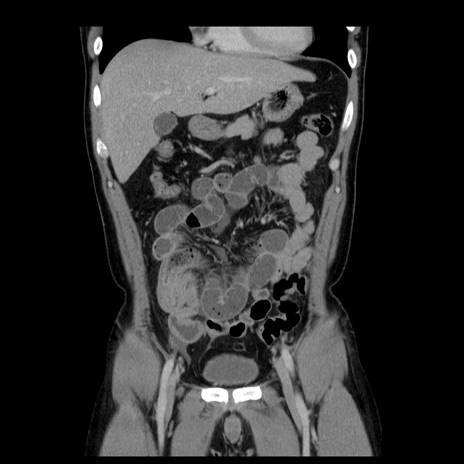

横断像

【症例】30歳代男性

【主訴】腹痛、嘔吐

【現病歴】昨晩から突然の腹痛あり、その後嘔吐、軟便も出現。腹痛が改善しないため救急搬送となる。2日前にしめ鯖の食事歴あり。

【身体所見】意識清明、苦悶様、BP 135/90mmHg、BT 35.7℃、腹部:平坦、やや硬、心窩部〜臍部に自発痛、圧痛あり、筋性防御+、反跳痛-

【データ】WBC 8100、CRP 0.57